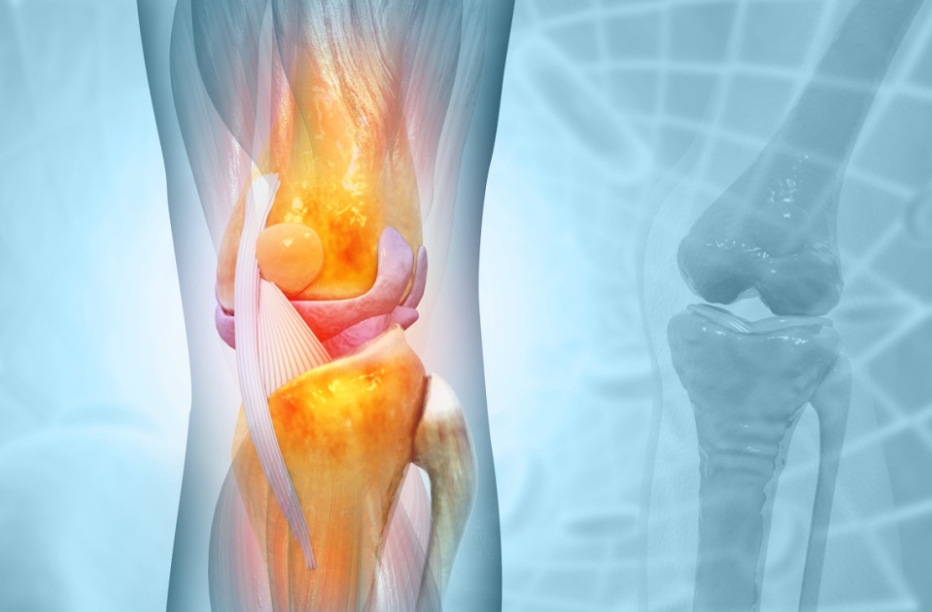

股骨头坏死作为一种进展性骨骼疾病,核心危害在于其不可逆的病理…… 【详情】

很多人认为股骨头坏死只是“髋部的问题”,即便不处理,顶多是走路…… 【详情】